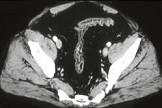

- 单项选择题男,41岁, 腹痛、腹泻、腹胀、脓血便、里急后重、疲乏无力,结合图像, 选择最可诊断  (    )

- A、溃疡性结肠炎

- B、结肠克罗恩病

- C、结肠结核

- D、假膜性肠炎

- E、结肠淋巴瘤